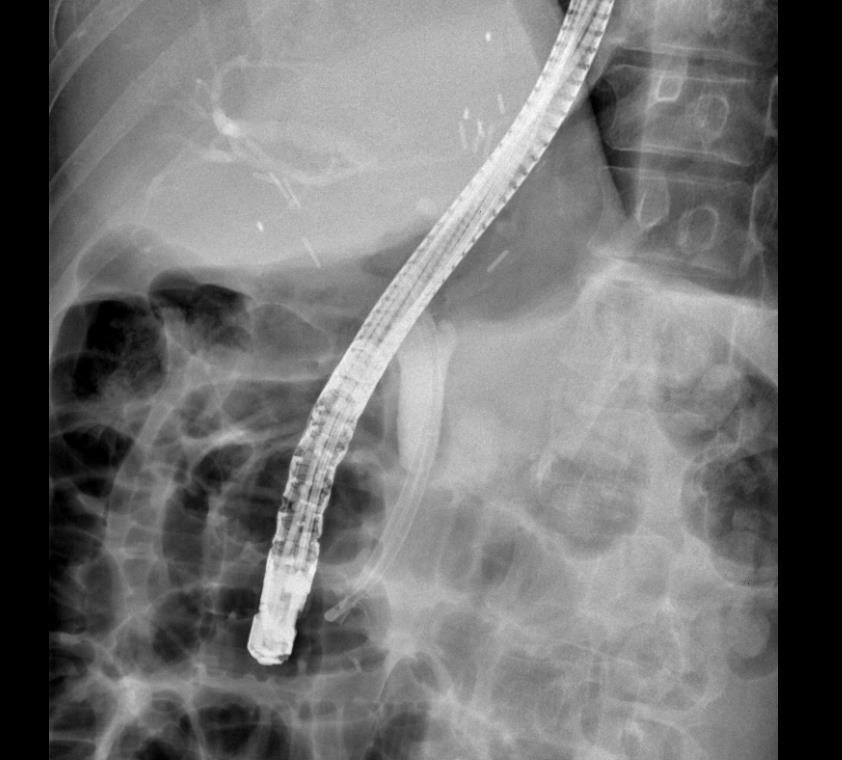

胆管癌梗阻性黄疸ERCP术中N多次想放弃。想想患者还是坚持了,成功那一刻的喜悦,吃再多的射线都是值得的